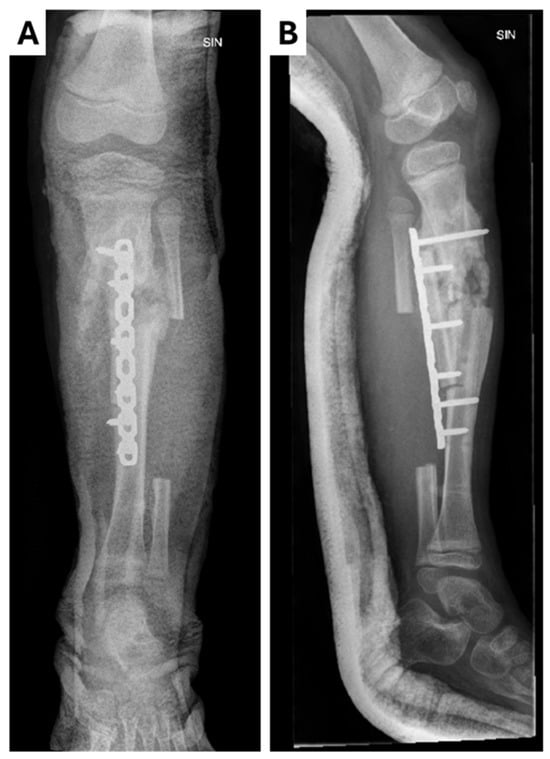

As no improvements in the patient’s dynamics were observed over the next 24 h, a surgical approach was considered: partial resection of the left tibia, cavity repair, and application of an external fixation device (Figure 2). The surgical site tissue and resected bone fragments were sent for histopathologic and microbiologic examinations. The patient was transferred to the Intensive Care Unit (ICU) for further monitoring and was administered metamizolum i/v 250 mg three times a day for pain management. A control echocardiogram (ECHO) performed in the ICU revealed mild mitral regurgitation, patent foramen ovale, and bilateral low-volume hydrothorax. Soft tissue cultures from the surgical site and blood cultures from the Regional Hospital both revealed Staphylococcus aureus infection (methicillin-sensitive, penicillin-sensitive). Oxacillin at 1000 mg six times a day was initiated based on the infectologist’s recommendations. The histopathological examination reported a morphological appearance consistent with acute osteomyelitis.

Figure 2.

Control X-ray of left leg in (A) anterior–posterior and (B) lateral projections after surgical manipulation and external fixation. During surgery, the rotation of the medial part of the tibia toward the fracture was performed along with the drainage of pus (~500 mL) around the fracture site. Pseudoarthrosis was observed during surgery along with the presence of infected cartilage tissue. Resection of the damaged bone was performed, resulting in limb shortening (~1 cm). A chlorhexidine impregnated material was left in the wound.